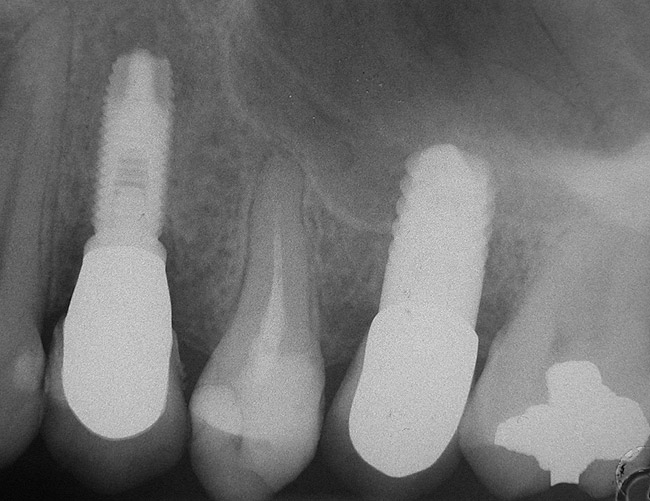

Figure 8  At 4 months after treatment, the radiograph revealed the presence of a bone layer surrounding the implant.

Figure 8

A full-thickness mucoperiosteal flap was raised, and alternating osteotomes were used to prepare the implant site. After achieving a length of 7 mm (Figure 7A and Figure 7B), heterologous bone graft was implanted and the osteotome sequence was repeated. The implant showed primary stability.

Second-stage surgery was performed after 4 months (Figure 8); healing abutments were placed and the soft tissue was allowed to heal for 5 more weeks. Then, splinted porcelain-fused-metal (PFM) crowns supported by custom gold abutments were delivered (Figure 9 and Figure 10).